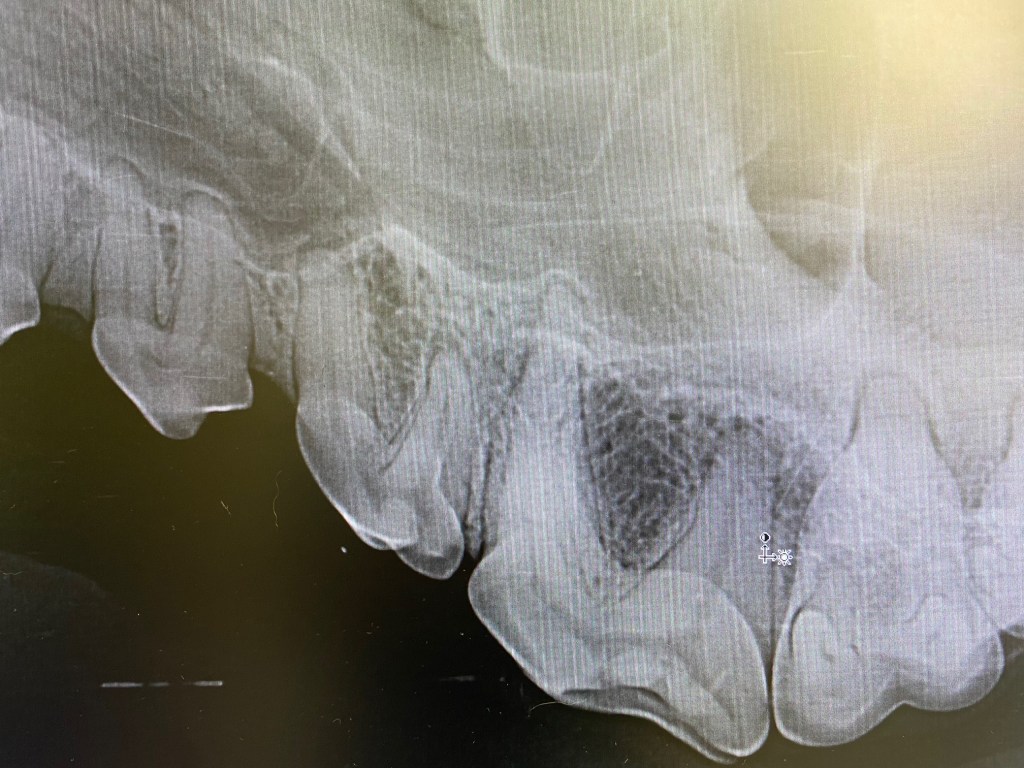

Slab fracture of 208x-ray at 45 degreesno sign of granuloma but as slab is below the gum line the tooth needs to be extractedInfraorbital and maxillary nerve blocks placedAll teeth descaled and polishedIncise to gingival junction with scalpel to distal edge of 209Place thumb on on infraorbital canal and make vertical incisionRaise a gingival flap using periosteal elevatorRound bur #6 to bur away buccal alveolar boneThe tooth sectioned at the furcationCrown removed and gutters cut using taper fissure burVet tome used to aid with extraction of distal root. Elevators and luxators also usedDistal root removed when looseDistal rootCrown height reduce on mesial roots until furcation visibleFurcation visibleBuccal root extracted with elevatorsTaper fissure bur used to remove the buccal bone of palatal rootPalatal root extracted using luxators, elevators and forcepsX ray to ensure all roots completely extractedRounded ends on sectioned roots indicate the root is fully removedCurette socketsFlush sockets with salineSmooth alveolar bone to ensure no rough edges with diamond football burMake periosteal releasing incision in the flap to ensure tension free closureSuture with 4/0 absorbable material simple interrupted patternClose up of extraction site after suturing